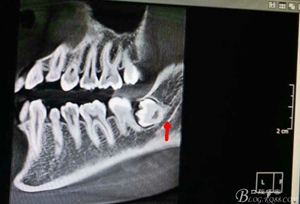

圖4.術(shù)前的CBCT縱剖面檢查:38牙根1/3緊鄰下頜管,看紅色箭頭。提示盡量不要斷根,如根尖折斷,取根導(dǎo)致下頜神經(jīng)損傷的風(fēng)險加大